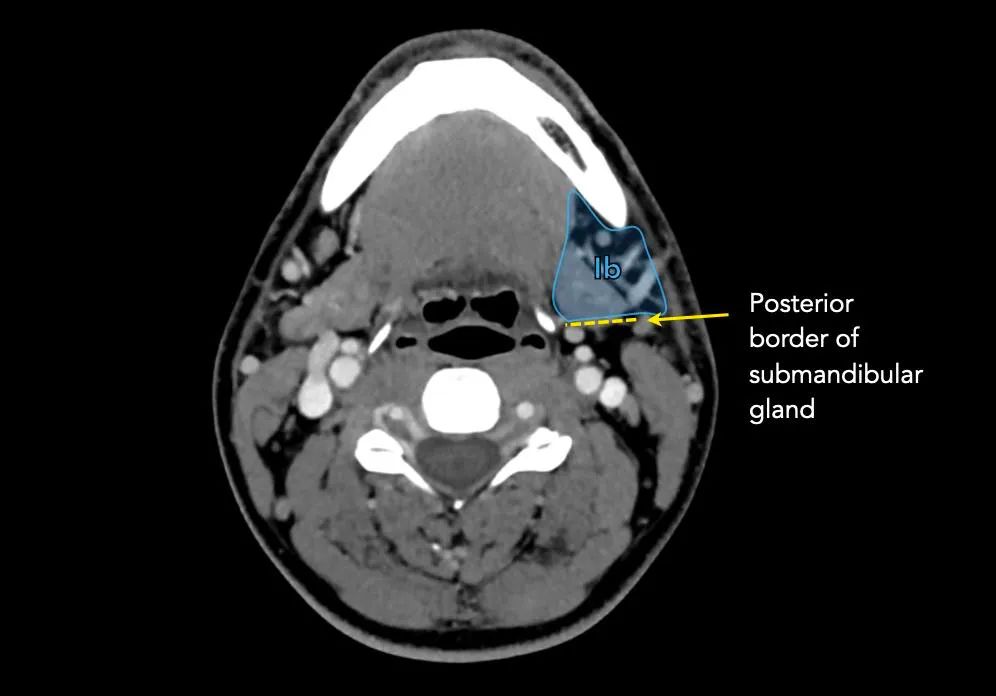

重要的地标是:

I级的淋巴结有从口腔、前鼻腔、面中部和颌下腺的软组织的癌症转移的风险。